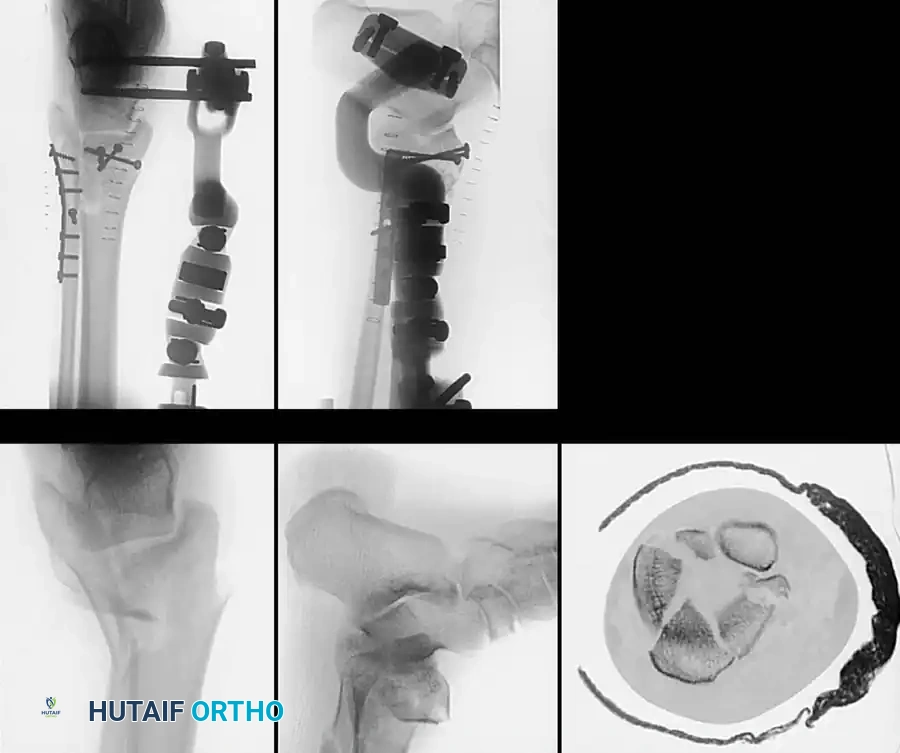

Complex Fracture Patterns and External Fixation

In cases of severe soft-tissue compromise (e.g., fracture blisters, massive edema, or open fractures), immediate internal fixation is contraindicated due to the high risk of wound dehiscence and deep infection.

In these scenarios, damage-control orthopedics is employed. A spanning external fixator is applied to restore length, alignment, and rotation while allowing the soft-tissue envelope to recover.

Once the "wrinkle sign" appears (typically 7 to 14 days post-injury), indicating resolution of edema, the patient is returned to the operating room for definitive ORIF.